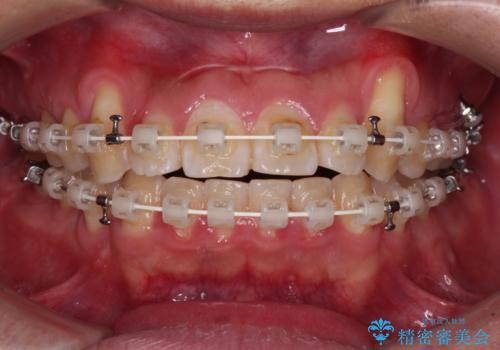

- 矯正装置

- 審美装置

- 八重歯と前歯の隙間を気にして来院された患者様です。

八重歯の改善のため、奥歯を後方に移動させていくこととし、患者様と相談の上、ワイヤー装置にて矯正治療を行うこととしました。

治療装置については、自己管理が煩わしいとのことで、マウスピースではなく目立ちにくいワイヤー装置を選択されました。